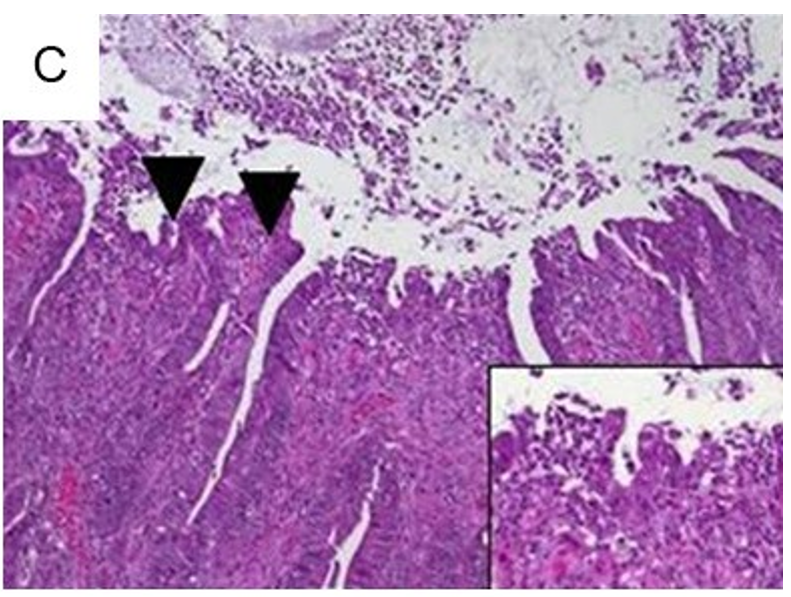

中性粒细胞散布在隐窝上皮细胞层中的隐窝炎(图3A)加剧至隐窝脓肿,中性粒细胞在隐窝腔内积聚,最终破坏隐窝上皮(图3B)。侵蚀,即表面上皮的缺失伴有潜在的炎症,其中主要是局灶性的上皮缺损达到基底膜。(图3C)

3(C)失去表面上皮,糜烂(箭头;×100,边框X400)。